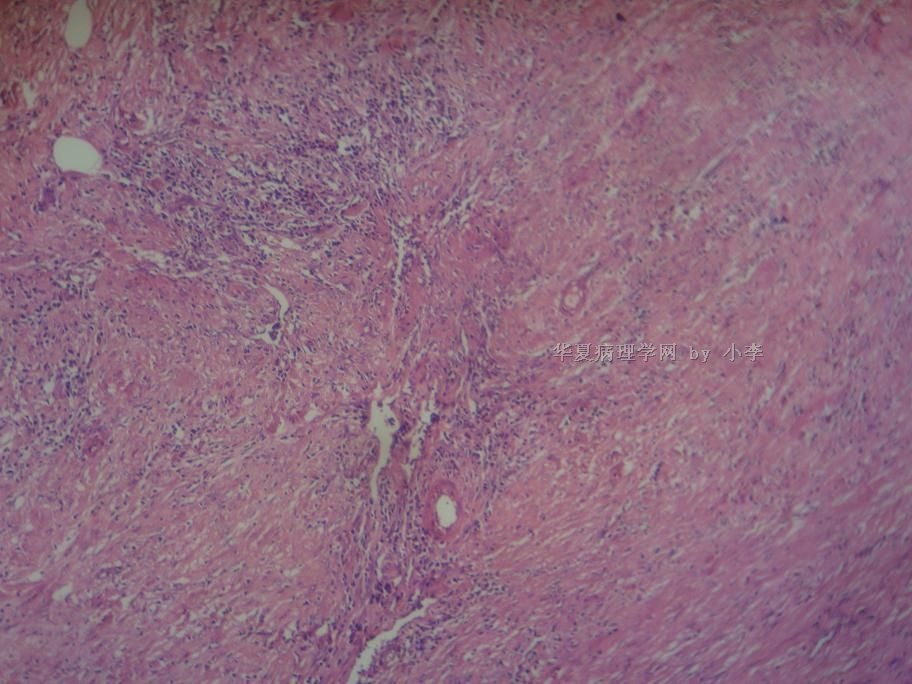

睾丸炎?

姓    名: ××× 性别:  男 年龄: 46岁

• 睾丸炎?图2

图2

首先考虑精子肉芽肿

慢性肉芽肿性炎

肉芽肿性睾丸炎

精子肉芽肿